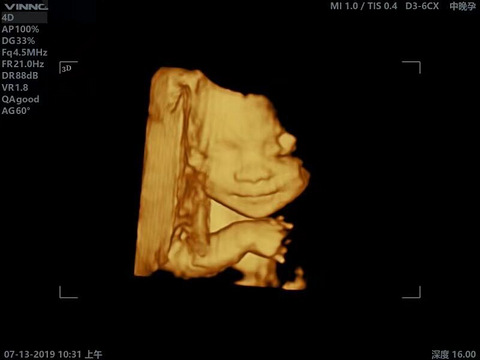

你们的四维照拍出来清晰吗?为什么我的糊糊的,点都不好看

看到别个孕妈妈晒的四维照,好清晰,而且宝宝好乖,居然还在笑。为什么我的糊糊的,点都不好看。你们的四维照拍出来清晰吗?